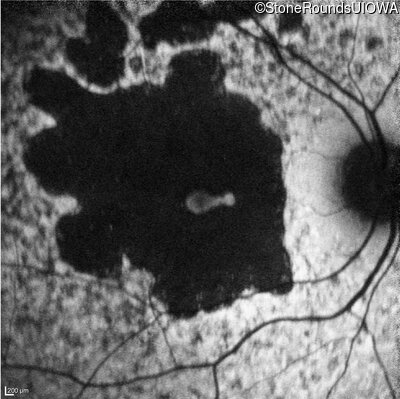

Age at visit: 30 years

This 30 year old man first noticed poor vision in dim light when he was five years old. His visual acuity began to fall in his early 20's.